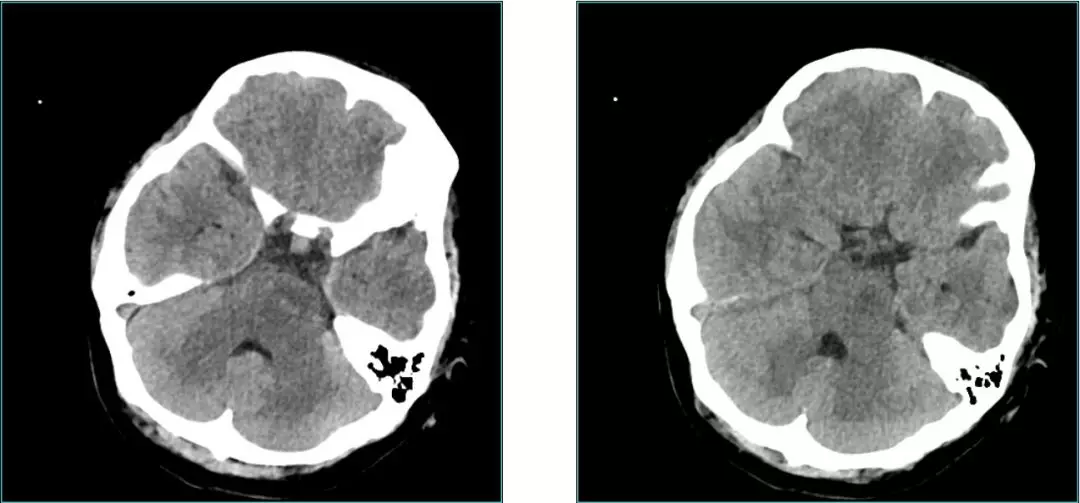

Pre-op CT scan

Pre-op CT Contrast

• 22y, Female headache , double Vision for 4 m;

• Examination:GCS 15 scores;abducens nerve palsy

• MRI Images:Reveals occupying lesions in pre-pon cistern, tumor with a upper clivus extension imbedding into brainstem from anterior.  Part of clivus bone is erosion.